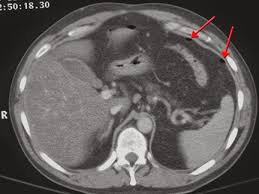

- Chụp CLVT dựng hình cây đường mật trong và ngoài gan được thực hiện nhằm bổ sung cho siêu âm, đặc biệt trong bệnh lý tắc mật. Hiện nay chụp CT dựng hình đường mật đang được ứng dụng thay thế chụp CLVT do có nhiều ưu điểm hơn.

- Bổ sung cho siêu âm trong chẩn đoán các bệnh lý gan mật (U, nhiễm trùng, sỏi…), bất thường hệ tiết niệu.

- Chỉ định chụp gan 3 pha: Xác định đặc điểm các tổn thương gan ngấm thuốc thì động mạch: u tế bào gan (HCC), di căn gan giàu mạch (Di căn ung thư nội tiết), các khối u gan lành tính (Adenoma, HNF…)

- Chỉ định chụp thông thường cho các khối u gan nghèo mạch (Di căn ung thư đại trực tràng), tăng áp tĩnh mạch cửa, tổn thương dạng nang (Áp xe, nang gan…)

- Nếu có tiêm thuốc, hình ảnh thể hiện rõ đúng các thì (Động mạch, tĩnh mạch):

- Thì động mạch: Thuốc cản quang chỉ ở trong các động mạch và không xuất hiện trong các tạng và nhu mô.

- Thì tĩnh mạch: Thuốc cản quang có ở cả trong động mạch, tĩnh mạch, các tạng và nhu mô.